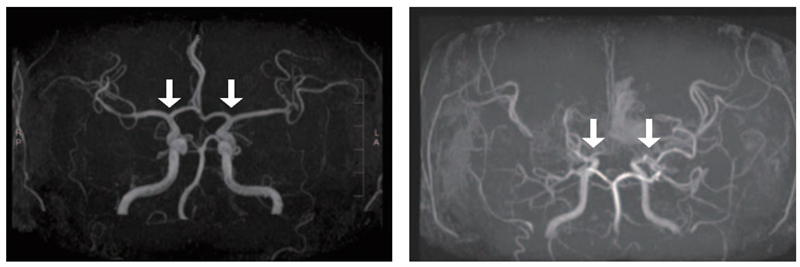

▲(왼쪽부터) 정상 및 모야모야병 환자의 뇌혈관

모야모야병은 뇌로 혈액을 공급하는 혈관이 원인 없이 점차 좁아지는 만성 진행성 뇌혈관질환이다. 10세 전후 소아와 40세 전후 성인에서 주로 발병하며, 부작용으로는 뇌혈관이 막히거나 파열되는 허혈성·출혈성 뇌졸중이 있다. 그중 소아 환자는 성인보다 허혈성 뇌졸중이 빈번하고, 장기 예후가 대체로 양호하지만, 3세 미만 어린 연령에서는 진행이 빨라 주의가 필요하다. 그러나 국내 소아 모야모야병 인구를 분석한 장기간 역학 자료는 제한적이었고, 이들의 예후를 분석한 결과도 드물었다.